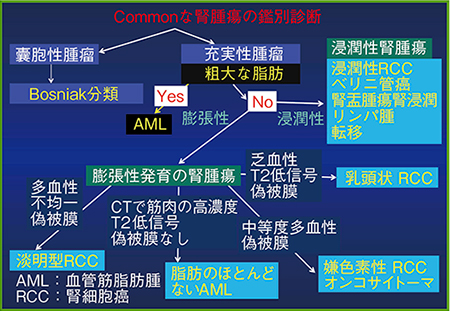

腎腫瘤の鑑別診断

腎腫瘤の診断ではまず,充実性腫瘤か囊胞性腫瘤かの鑑別が必要となる(図1)。嚢胞性腫瘤であれば,Bosniak分類に当てはめてカテゴリーを評価する1)。Bosniak分類は元来,造影CTによる分類であり,造影MRIを用いるとカテゴリーが上がると言われている2)。

図1 腎腫瘤の鑑別診断フローチャート

充実性腫瘤であれば,腎細胞癌との鑑別は重要である。粗大な脂肪があれば良性の腎血管筋脂肪腫と診断される。粗大な脂肪がなければ,次に浸潤性か膨張性かを区別する。

腎癌は浸潤性腎癌を除けばほとんど膨張性に発育し,なかでも組織型で淡明細胞癌が7〜8割を占める。淡明細胞癌は細胞質中に脂質を含むため,MRIで検出することができる。

多血性で,偽被膜を有する淡明細胞癌のMRIでは,中に出血性壊死があるため,T2強調画像で不均一な信号を示す。偽被膜の描出には,MRIのT2強調画像が最も適している。偽被膜が破れていなければ,その腫瘤が限局性であることがわかり,部分切除の指標に役立つ。また,偽被膜の有無によって,ある程度の腫瘤の鑑別にも役立つと言える。

また,腎腫瘤のタイプは血流でも鑑別できるが,MRIのT2強調画像における信号の違いも役に立つ(図2)。特に,淡明細胞癌はin phaseに比べてopposed phaseでは低信号となることがある(図3)。